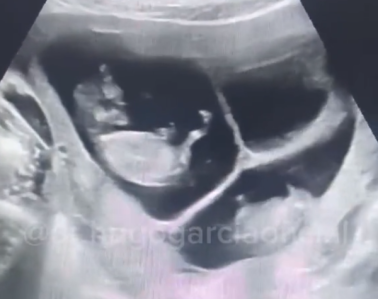

No registro o médico, Hugo Garcia, contava uma história para os pais enquanto fazia um ultrassom.

Quando contou sobre o terceiro e mostrou o ultrassom, o pai das crianças teve uma reação inusitada e desmaiou durante a consulta. O médico, então, parou de gravar o vídeo e foi socorrê-lo.